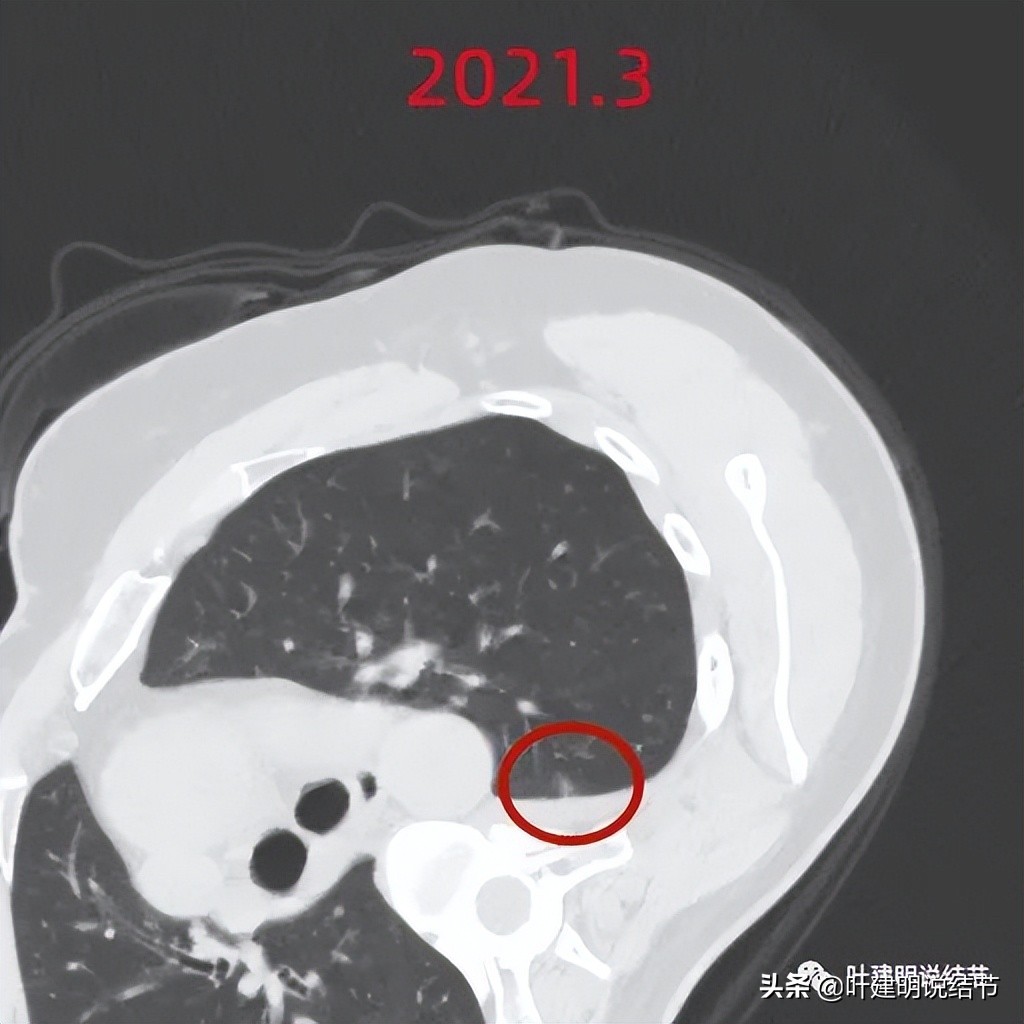

我们先来看她的2021年3月CT图像:

上图是较大的病灶,但密度很低,轮廓较清,但瘤肺边界偏模糊,似见血管进入,由于密度低,风险不大,当时嘱随访。

上图是较小的病灶,密度较差大病灶高,但它其小,邻近胸膜,偏长条状,感觉也是不典型增生可能性大,也嘱随访。